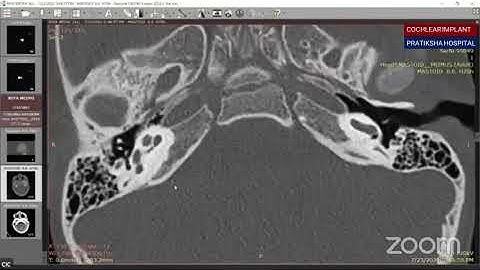

Imaging for cochlear implants 1